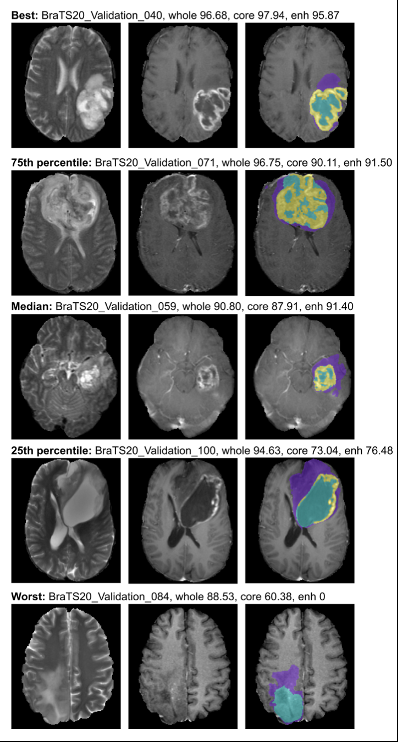

更多的分割结果如图3-6所示,包括不同程度肿瘤的分割情况。

图3-6 验证集分割结果定性分析